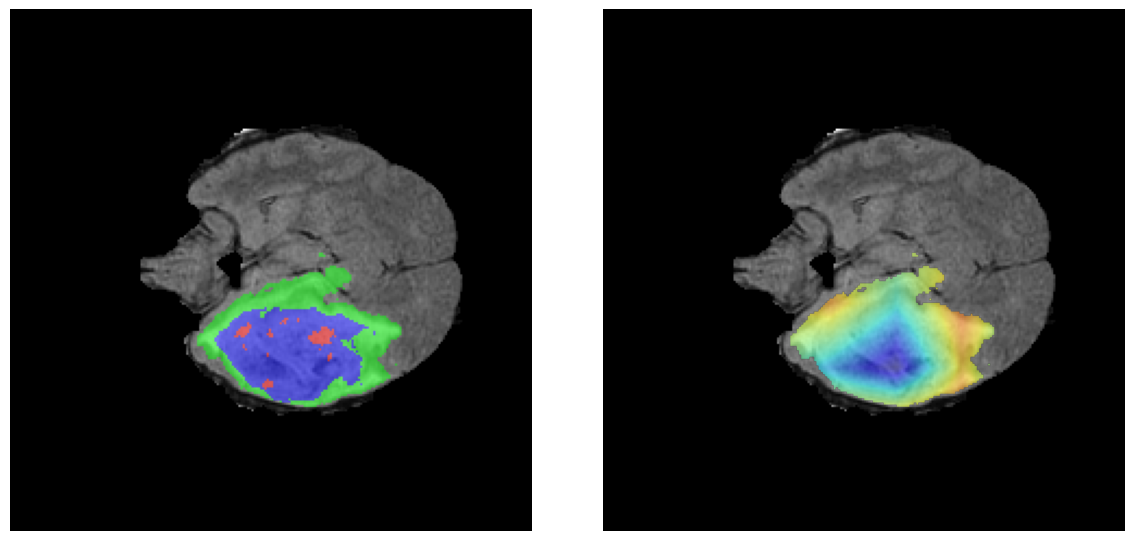

Mapas de Explicabilidad (Grad-CAM++)

Visualización de las regiones de atención del modelo que validan su razonamiento clínicamente relevante

Ejemplos HGG - Atención en Núcleo Necrótico y Tumor Realzado

HGG Grad-CAM++ 1 HGG Grad-CAM++ 2 HGG Grad-CAM++ 3 HGG Grad-CAM++ 4 HGG Grad-CAM++ 5 HGG Grad-CAM++ 6

Los heatmaps muestran que el modelo concentra su atención en las regiones de Tumor Realzado (rojo) y Núcleo Necrótico (azul), características patológicas clave de los gliomas de alto grado.

Ejemplos LGG - Atención Difusa en Edema Peritumoral

LGG Grad-CAM++ 1 LGG Grad-CAM++ 2 LGG Grad-CAM++ 3 LGG Grad-CAM++ 4 LGG Grad-CAM++ 5 LGG Grad-CAM++ 6

Para casos LGG, la atención del modelo es más difusa y se concentra principalmente en la región de Edema Peritumoral (verde), consistente con la naturaleza más infiltrativa y menos agresiva de estos tumores.

El análisis Grad-CAM++ reveló que el modelo desarrolla automáticamente la capacidad de localizar las regiones tumorales. Para casos HGG, la atención se alinea fuertemente con las regiones de Tumor Realzado (ET) y Núcleo Necrótico (NCR). En contraste, los casos LGG muestran atención más difusa, principalmente concentrada en la región de Edema Peritumoral (ED), lo cual es consistente con la patofisiología conocida de los gliomas.